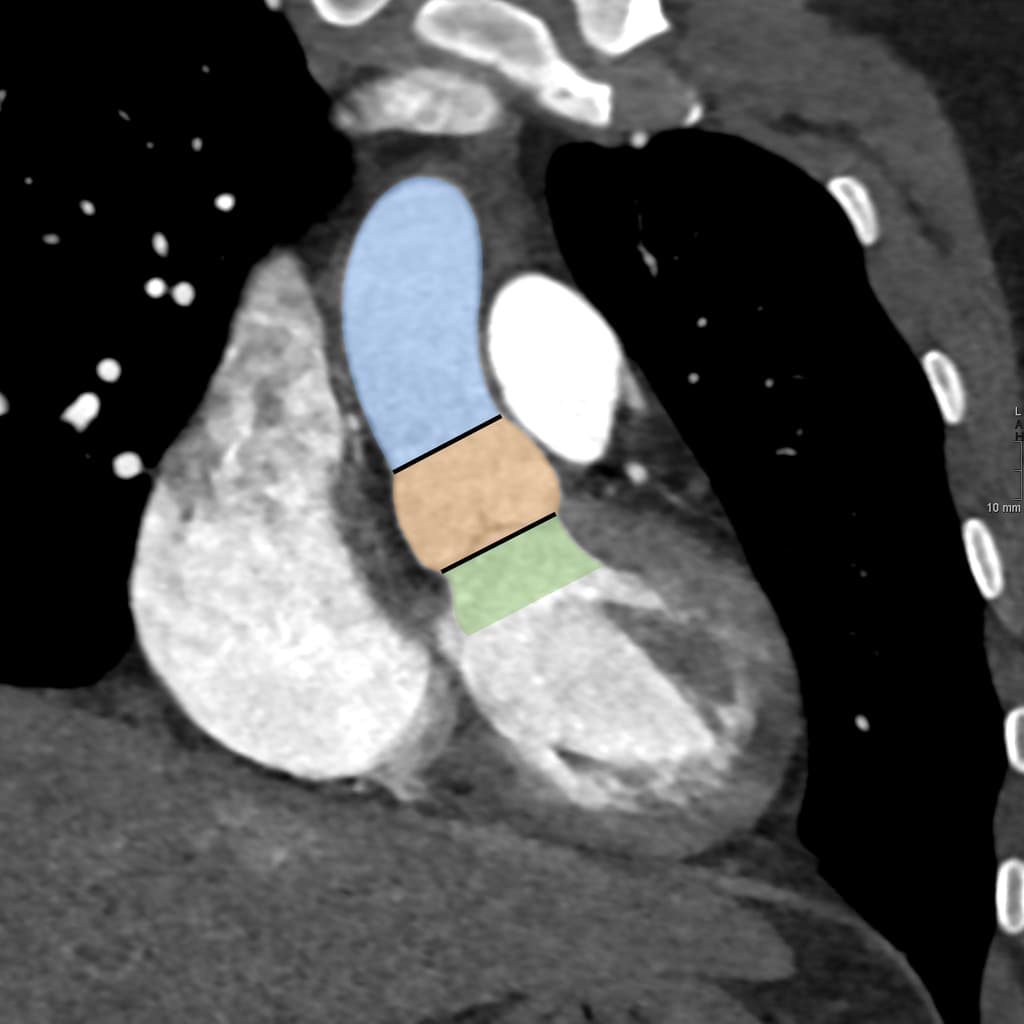

- Hình ảnh CTA mặt cắt vành chếch (oblique coronal CTA) của gốc động mạch chủ (aortic root) cho thấy các cấu trúc giải phẫu liên quan.

- Gốc động mạch chủ (aortic root) nằm giữa vòng van động mạch chủ (aortic annulus) (vị trí nối giữa đường ra thất trái [left ventricle outflow tract] và van động mạch chủ [aortic valve]) và chỗ nối xoang ống (sinotubular junction) (nơi bắt đầu của động mạch chủ lên [ascending aorta]).

- Các kích thước này là cần thiết để lập kế hoạch thay van động mạch chủ qua ống thông (TAVI planning).

- "Gốc động mạch chủ kéo dài từ vòng van động mạch chủ đến chỗ nối xoang ống."

- "Đo đạc chính xác gốc động mạch chủ là rất quan trọng để lập kế hoạch TAVI."

- "Gốc động mạch chủ bao gồm các xoang Valsalva và các lá van động mạch chủ."

Gốc động mạch chủ là một vùng giải phẫu phức tạp nằm giữa đường ra thất trái và động mạch chủ lên. Nó bao gồm vòng van động mạch chủ, các xoang Valsalva và chỗ nối xoang ống. Đánh giá chính xác các cấu trúc này trên chụp cắt lớp vi tính mạch máu (CTA) là điều cần thiết để lập kế hoạch trước thủ thuật thay van động mạch chủ qua ống thông (TAVI), đảm bảo kích thước và vị trí đặt van nhân tạo chính xác.